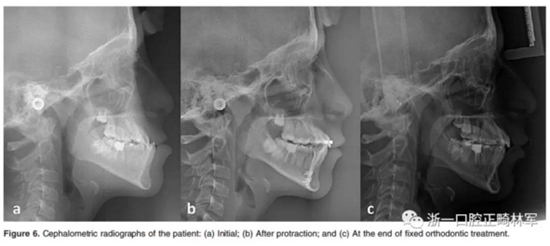

在開合關(guān)閉后,并用直絲弓技術(shù)繼續(xù)治療。在固定正畸治療過程中,有5位患者拔除上頜前磨牙,以解除擁擠和II類尖牙關(guān)系。對于正在生長發(fā)育的III類患者夜間佩戴bianator。治療前后拍攝頭顱側(cè)位片。Figure 5和Figure 6顯示了該組中的一名患者的治療過程。

觀察、牽引、正畸治療的時間分別為5.36±1.48個月,3.85±1.12個月和23.13±7.03個月。Table 1和Table 2列出了頭影測量的數(shù)據(jù)。Table 3和Table 4顯示了三個時期的差異以及這些時期的統(tǒng)計比較。在觀察期間,矢狀面骨骼參數(shù)無顯著變化。在牽引階段,A點向前運動3.59±1.32 mm(P<0.01),B點向后運動為1.85±1.46 mm(P<0.01)。上頜骨和下頜骨的骨骼變化導(dǎo)致ANB顯著改善(-4.18±1.47°,P <0.01,見Table 3)。固定正畸治療期間矢狀面骨參數(shù)沒有明顯變化。

關(guān)于垂直參數(shù),在觀察期間沒有觀察到顯著變化。在牽引期間,SN-UOP角度(8.28±4.41°,P<0.01)顯著下降,在固定正畸治療后其又明顯上升(- 4.51±6.19.75mm; P <0.01)。此外,SN-MP,F(xiàn)MA和NMe在牽引階段均呈上升趨勢,除SN-MP以外,這幾個指標(biāo)在的固定正畸階段均無明顯變化。在固定正畸治療期間,S-Go顯著增大(-2.34±2.16mm; P<0.01)(Table 3)。

在觀察期間牙齒參數(shù)沒有發(fā)現(xiàn)顯著變化。但是在牽引期間,上下切牙分別唇傾9.66±5.26°和3.63±6.316°。在正畸期間,上切牙直立6.26±6 4.76°,而下切牙傾斜角度保持不變。上頜磨牙前移(-5.59±2.94 mm; P<0.01),下移(2.97±2.11 mm; P<0.01),在固定正畸過程中保持不變(Table 4)。

在觀察期間顯示唯一增加的軟組織參數(shù)是鼻尖點(-0.73±0.21mm; P<0.05)。然而,在牽引過程中,上唇向前移動,頦前點朝后移動(1.71±1.84 mm; P<0.01),鼻尖點前移(-2.56±1.20 mm; P<0.01),所有這些變化在整個固定正畸過程中保持不變(Table 4)。